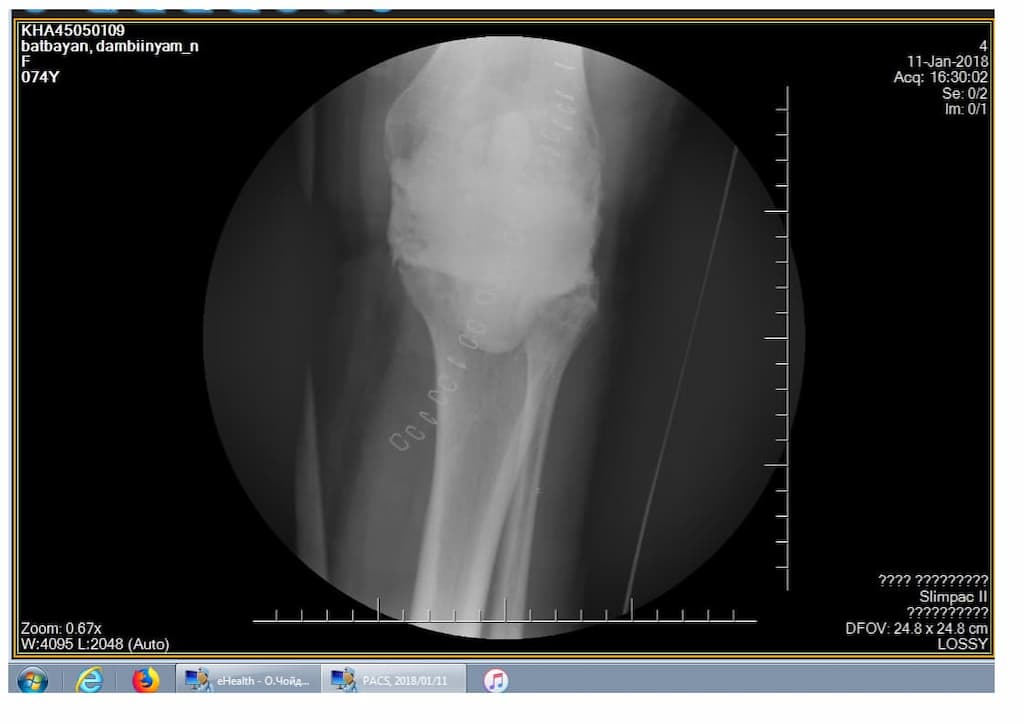

Өвчтөн: Н.Х 74 настай, эмэгтэй 2018.9.14

Сэргээн засах мэс засал: Шилбэний хиймэл үений ховхролыг сэргээх тусгай протез суулгах мэс засал.

Үе дайрсан ясны анхдагч хавдар, ясны дутмагшлын үед хийгдэх мэс засалimg27Үе дайрсан ясны анхдагч хавдар, ясны дутмагшлын үед хийгдэх мэс засалimg28

Зураг 1. Сэргээн засах мэс заслын өмнөх рентген зураг. Эгц урд, хажуугаас авсан байдал. Халдварын бус шалтгаант хиймэл үений ховхрол.